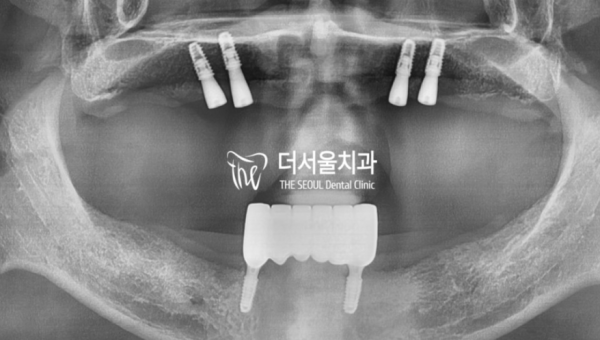

엑스레이 사진을 통해 환자분의 치조골을 확인해보았습니다.

뼈가 거의 없는 상태였기 때문에 임플란트를 심는것도 어려운 상태입니다.

I checked your alveolar bone through X-ray.

It's also difficult to plant an implant because there was almost no bone.

이렇게 아주 구체적이고 정확하게 임플란트 식립계획을 컴퓨터로 확인합니다.

이 환자분은 상악에 최소개수의 임플란트를 식립한 후에 보철을 결합하고

하악은 전치부에 식립한 후 구치부 가철성 보철을 하기로 하였습니다.

This is a very detailed and accurate computer-check of the implant placement plan.

This patient has placed at least one implant in the maxilla, then combined the prosthesis

After placing the mandible in the anterior teeth, it was decided to have an iron prosthesis in the posterior teeth.